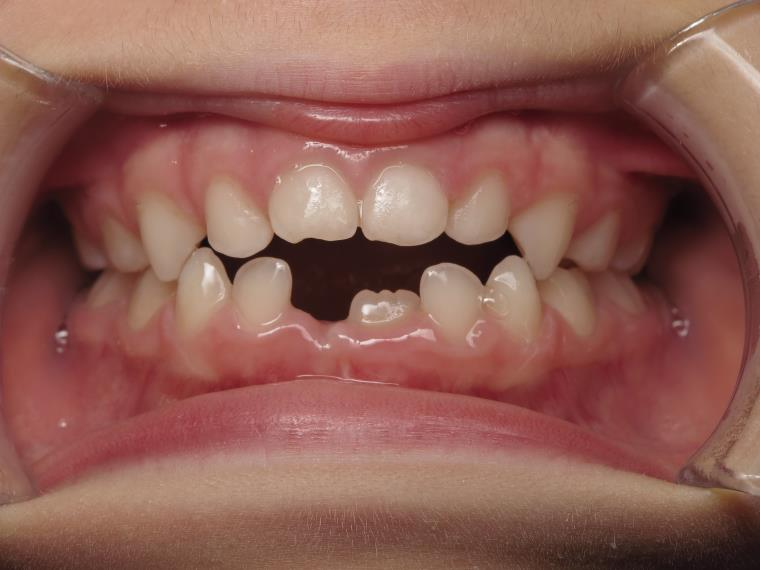

14 béance inversé gauche 5 ans

inversion postérieur coté droit et espace entre l'arcade du haut et du bas (béance)

bilan début et en cours de traitement